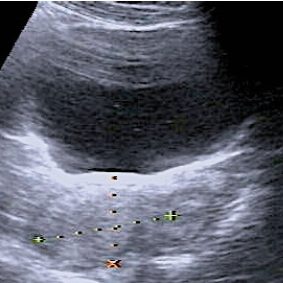

L’échographie endo-vaginale est l’examen de choix pour reconnaître le caractère bénin ou malin d’une tumeur ovarienne : 10 règles simples facilitent l’interprétation des images échographiques. ■ Introduction : le cancer de l’ovaire En Allemagne, une femme sur 72 développe un cancer de l’ovaire (1). L’âge moyen au moment du diagnostic est de 69 ans, mais la fréquence augmente…